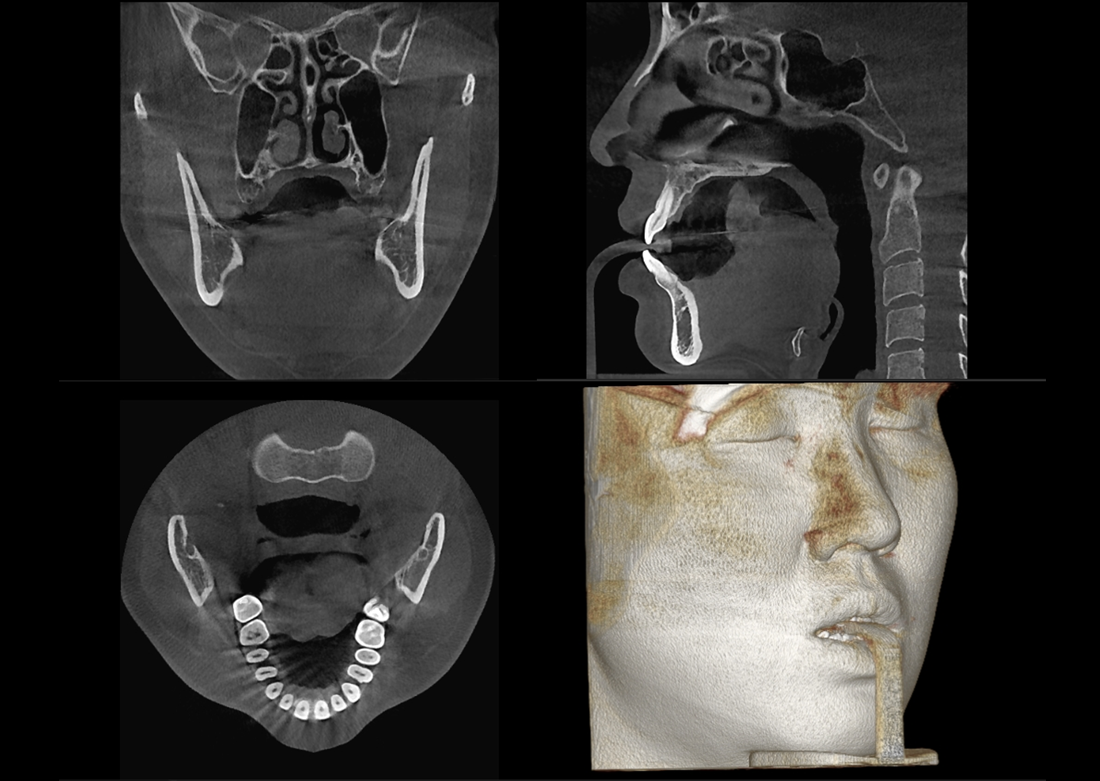

KLİNIKAI KÉPEK

Kiváló diagnosztikai képalkotás több éves tapasztalattal és szakértelemmel.

A Genoray büszkesége, amelyet világszerte elismernek és szeretnek.